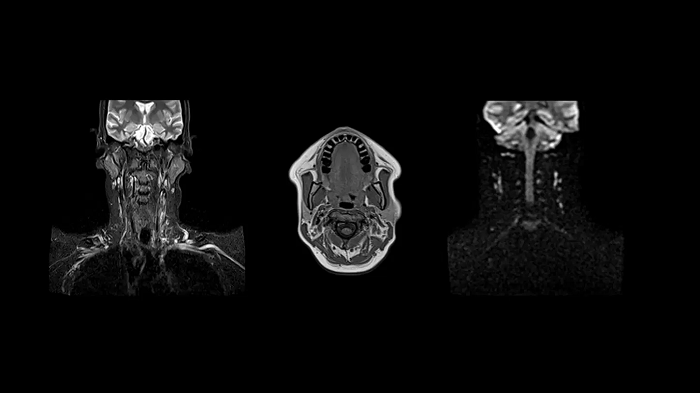

Neck

Excellent soft tissue contrast in the neck

All-inclusive soft tissue examination of the head with outstanding image quality for T1, T2, and diffusion contrast.

- Head/Neck Coil

- Spine Coil

Image Courtesy: University Hospital Erlangen, Germany | Image-ID: 4aaaa0458

Spine

C-Spine - T2 TSE

Integrate Head/Neck and Spine Coil to gain outstanding C-Spine images with T2 TSE.

Image Courtesy: University Hospital Erlangen, Germany | Image-ID: 4aaaa0440